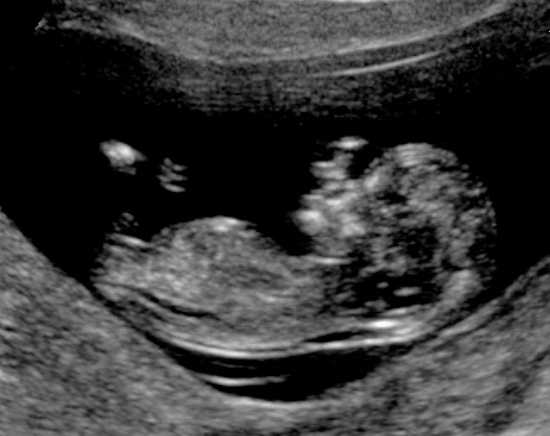

12 week scan of Dot! Our number three on the way! Everything is looking fine, due date of June 22, 2017 and funnily enough, this is 3 years to the day that we had Iris' 12 week scan.